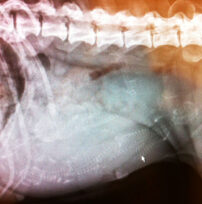

49 dage efter parringen kan man tage et røntgenbillede af tæven. Her kan man se hvalpenes knogletegning. Dette er den bedste måde at vurdere, hvor man hvalpe man skal forvente.